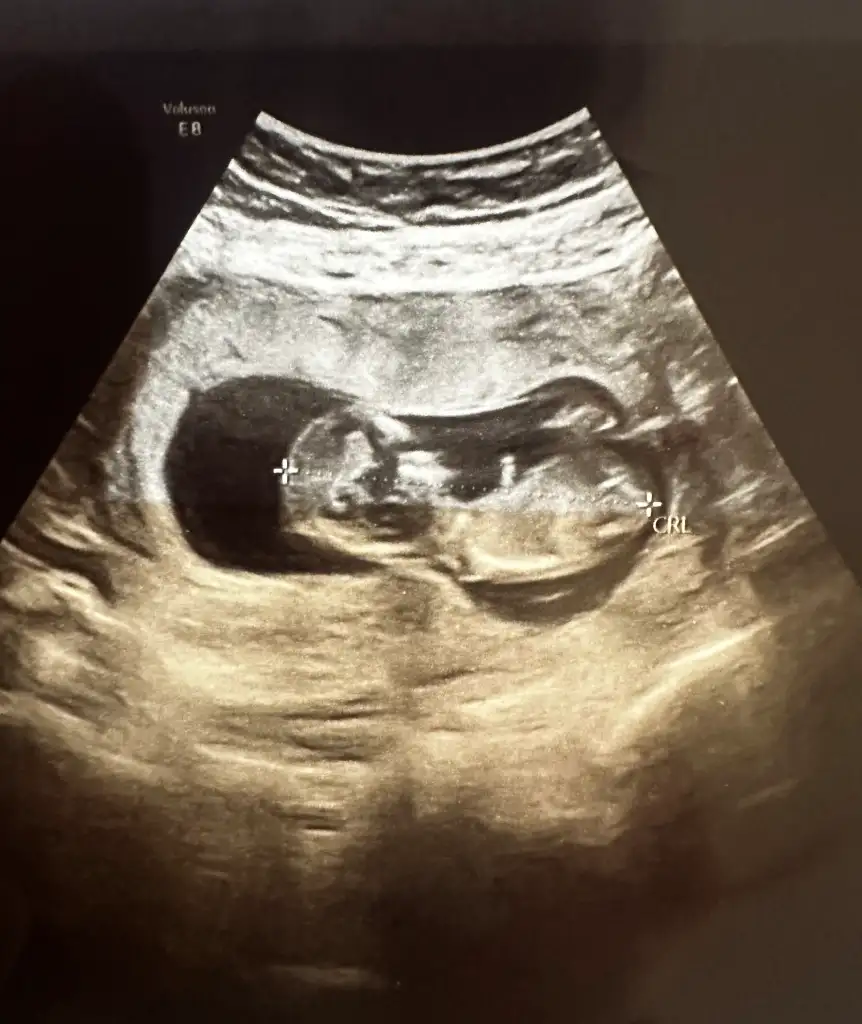

Bana da yorum yapar mısınız ? Arada gibi sanki erkeğin 1. Fotosuna da benziyor kızın 3.fotosuna da ben anlayamadımİnternetten nub teorisi diye arastır sende tahminde bulunabilirsin :)

Kese şekliyle ilgisi yok bence ama nub doğruDemek yuvarlak kese her zaman kiz degil)

Nub nasil oluyorki? Hala anlayamadim. 30 derecelik aciya gore dimi? Ben en son 10+2de ultrason muayenesinde oldum. Bi fark olur mu 2 haftada?Kese şekliyle ilgisi yok bence ama nub doğru